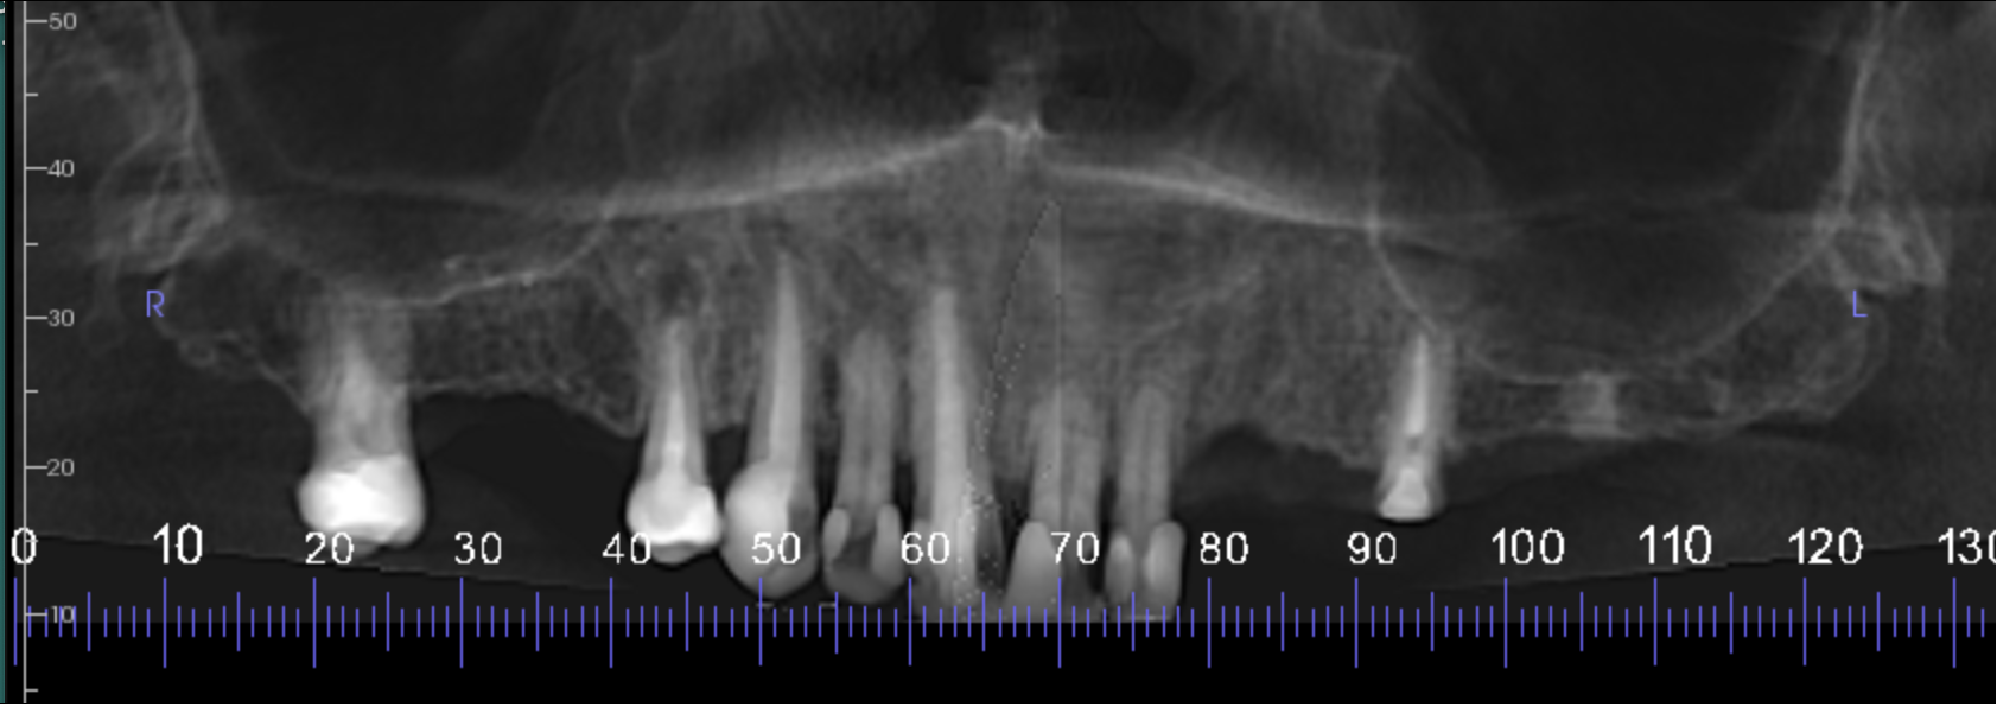

Reconstructed panoramic view of the maxilla

The edentulous regions have mild to moderate vertical bone resorption with moderate density cortical and trabecular bone. The UL7 edentulous ridge has a well-defined radiopacity measuring 4 x 3 x 6 mm, extending from the alveolar crest to the sinus floor. This is a dense bony island or retained root tip.

The UR3, UR1 and UL5 are root treated to apices with normal periodontal ligament spaces.

The UR4 is root treated. The buccal root filling is short of the apex with an apical radiolucency 3-4 mm wide. This is probably an apical granuloma or radicular cyst secondary to chronic apical periodontitis. The palatal root canal is filled to the apex with an apical radiolucency 0.5-1 mm wide.

The UL1 has external root resorption, mostly on the palatal side of the root. Approximately a third to half of the root is resorbed. There is no apical radiolucency but the root may be partially ankylosed to the bone. The UL2 also has external root resorption but to a lesser extent.